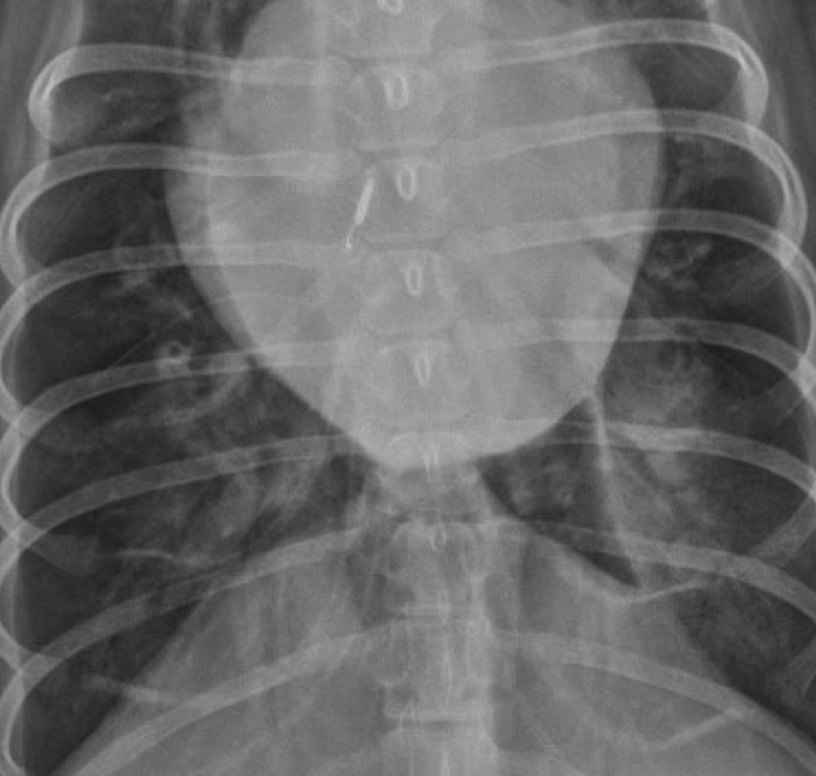

what type of pattern

right caudal lobe: intersitial- can still see vessels

left caudal lobe- alveolar- can not see vessels, can see air bronchiogram

cardiogenic pulmonary edema

left sided cardiomegaly- left auricular bulge